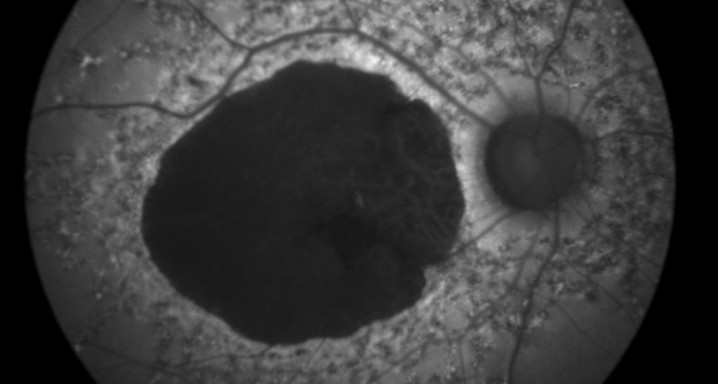

Autofluorescencia 25/03/2013

Las imágenes de autofluorescencia del fondo del ojo son una técnica no invasiva que proporciona información detallada del surgimiento y evolución de la enfermedad.

La técnica de autofluorescencia usa las propiedades fluorescentes de un indicador metabólico llamado lipofuscina para estudiar la salud y la viabilidad del complejo epitelio pigmentario de la retina (EPR). Mientras que en la retina exterior existen otros fluoróforos que pueden aparecer con la enfermedad, la lipofuscina es la principal fuente de fluorescencia intrínseca del fondo ocular. Una acumulación excesiva de gránulos de lipofuscina en el compartimiento lisosómico de las células del EPR representa una ruta común patogénica para varias enfermedades retinianas complejas y hereditarias, como la DMAE.